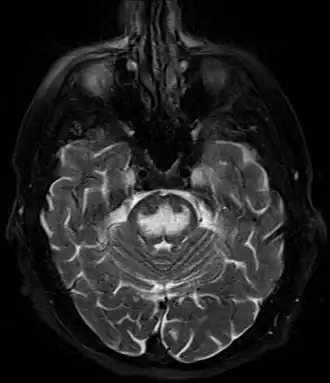

- Нейровизуализация: компьютерная томография как скрининговый метод. В первую очередь для исключения другой патологии головного мозга. Магнитно-резонансная томография. Возможно использование позитронно-эмиссионной томографии (ПЭТ).

- Визуализация головного мозга при синдроме осмотической демиелинизации[18]

- Магнитно-резонансная томография (МРТ)

Чаще изменения локализуются в нижней части моста имеют вид трезубца или бабочки. Но могут быть также в базальных ганглиях, среднем мозге и белом веществе субкортикальных областей. Накопление контрастного вещества возможно.

Ранние изменения (в первые 24 часа от развития тетрапареза): гиперинтенсивный сигнал (что говорит об ограничении диффузии) в режиме DWI. Изменения в режимах Т1- (гипоинтенсивный сигнал) и Т2-ВИ (гиперинтенсивный) могут развиваться не сразу (до 2 недель). Другие последовательности: FLAIR: гиперинтенсивный, ADC: низкий сигнал